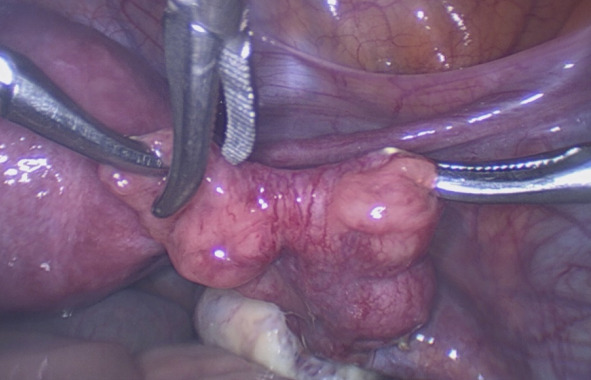

Materials and methods: The investigation was carried out in five medical centres in China and France from February to July 2021 and included reproductive-age patients who underwent gynaecological laparoscopy. Subtle abnormalities included Hydatid of Morgagni (HM) , fimbrial agglutination, tubal diverticula, accessory ostium, fimbrial phimosis, and accessory fallopian tube.

Results: 642 patients were enrolled in the study and 257 (40.0%) were diagnosed with subtle tube abnormalities. Hydatid of Morgagni was the most common abnormality (22.7%; n=146), followed by fimbrial agglutination (19.8%; n=127), tubal diverticula (6.9%; n=44), accessory tube (2.0%; n=13), and tubal accessory ostium (1.9%; n=12). Fimbrial phimosis was the least common abnormality (0.3%; n=2). The prevalence of subtle fallopian tube abnormalities was significantly higher among infertile patients (188/375, 50.1%) than those without history of infertility (69/267, 25.8%, ᶍ2=38.332, P=0.000). 209 patients were diagnosed with endometriosis during surgery, and the prevalence of subtle abnormalities was significantly higher in the endometriosis group than in those without endometriosis (61.2%, [128/209] vs. 29.8% [129/433], ᶍ2=58.086, P=0.000).

Abstract Image